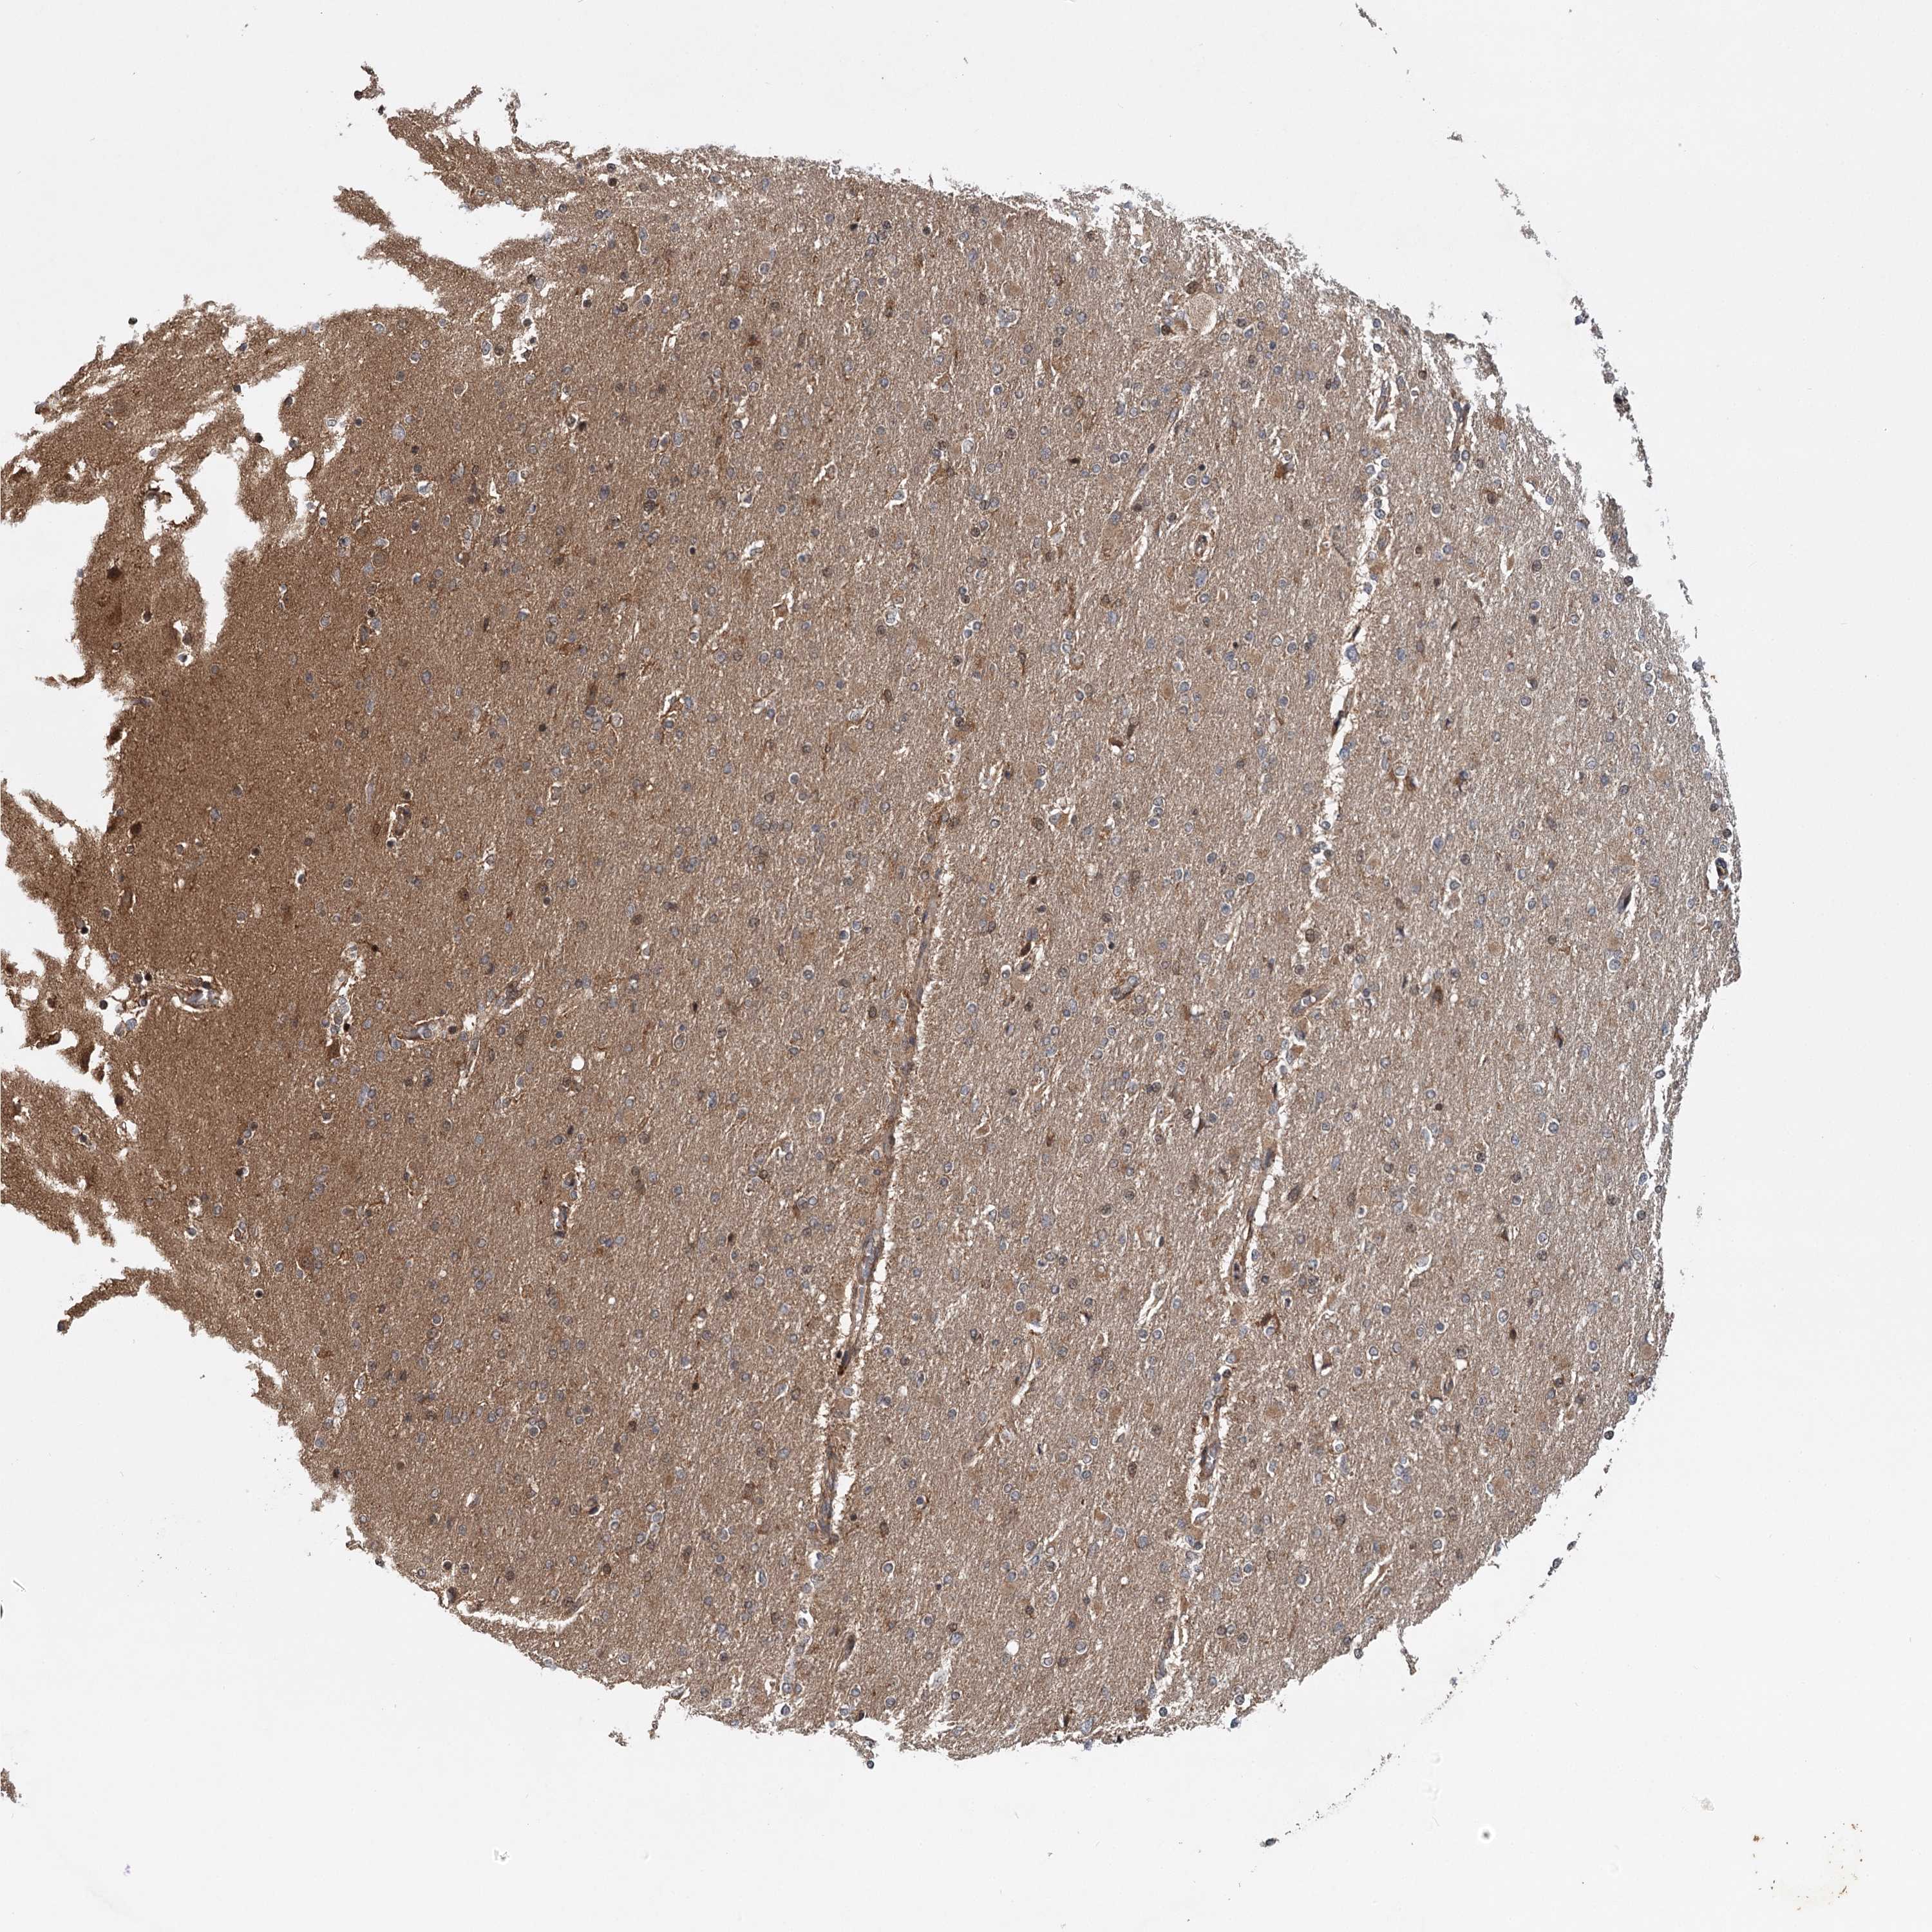

GLIOMA - Protein expressioni

A mouse-over function shows sample information and annotation data. Click on an image to view it in a full screen mode. Samples can be filtered based on level of antibody staining by selecting one or several of the following categories: high, medium, low and not detected. The assay and annotation is described here.

Note that samples used for immunohistochemistry by the Human Protein Atlas do not correspond to samples in the TCGA dataset.

Antibody stainingi

Antibody staining in the annotated cell types in the current human tissue is reported as not detected, low, medium, or high, based on conventional immunohistochemistry profiling in selected tissues. This score is based on the combination of the staining intensity and fraction of stained cells.

Each image is clickable and will lead to virtual microscopy that enables deeper exploration of all samples and also displays staining intensity scores, fraction scores and subcellular localization as well as patient and tissue information for each sample.

Antibody CAB033861

Staining

High

Medium

Low

Not detected

Intensity

Strong

Moderate

Weak

Negative

Quantity

>75%

75%-25%

<25%

None

Location

Nuclear

Cytoplasmic/membranous

Cytoplasmic/membranous,nuclear

Glioma, malignant, High grade

Glioma, malignant, Low grade

Glioblastoma, NOS